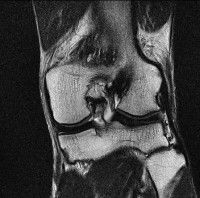

무릎 mri 간단히 봐주실 수 있으시나요 ㅠㅠ

안녕하세요 8년전 십자인대 수술하고 최근 무리한 운동에 무릎 불편감이 생겨서

mri 찍었습니다.

진단결과는 첫 찍은 병원에서 활액막염 이라는 진단을 받았습니다. 혹시 봐주실 수 있으실까요?

올라온 MRI가 단편적이라서 정확한 진단에 어려움이 있지만 십자인대에는 큰 이상이 있지는 않은것 같으며, 무릎관절내 물이 있는 것으로 보아 활액막염의 진단이 맞을 것 같습니다.

하지만 단편적인 영상이기 때문에 촬영병원에서 정확한 판독지 등을 받으시는 것이 좋겠습니다.